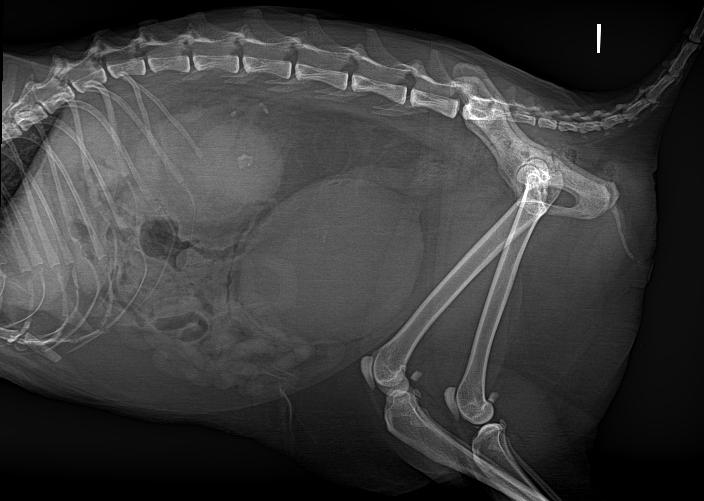

Un perro macho no castrado de raza boxer de 7 años de edad fue derivado al servicio de medicina interna por presentar una cojera causada por una posible neoplasia ósea. El paciente había acudido inicialmente al centro referidor con una cojera de la extremidad pelviana derecha de dos meses de evolución. Se habían realizado radiografías de las extremidades pelvianas donde se había observado una lesión lítico-proliferativa en el fémur derecho de la que se tomó biopsia sin obtener un diagnóstico definitivo. En nuestro centro, los tutores comentaron que el paciente estaba apático y con heces intermitentemente blandas. Durante la exploración física, el paciente presentaba una buena condición corporal (5/9), linfadenopatía poplítea derecha y una cojera con apoyo de la extremidad posterior derecha sin zonas engrosadas a la palpación ni puntos dolorosos. Se palpó, además, una masa cer-

Posteriormente y bajo anestesia [metadona (Metasedin, Esteve, Barcelona) a 0,2 mg/kg IV, dexmedetomidina (Dexdomitor, Zoetis, Barcelona) a 1 µg/kg IV y propofol (propofol Lipuro, Bbraun, Barcelona) a 3 mg/kg IV], se efectuó un estudio de TC de cuello, tórax, abdomen y extremidades torácicas y pelvianas (Aquilion 16 cortes, Canon Medical, Madrid).

Se realizaron series precontraste y postcontraste en fase venosa temprana con iohexol (Omnipaque 300 mg/ml, GE Healthcare, Barcelona) a 600 mg/kg IV, administrado a 3 ml/s mediante inyector automático (Medrad Stellant, Bayer Medical Care, Maastricht), y que se evaluaron con algoritmos de tejido blando, pulmón y hueso con cortes de 2 mm de grosor.

En la diáfisis media y metáfisis distal del fémur derecho, se visualizó una lesión ósea con características agresivas (Fig. 1). Presentaba un aumento de atenuación de la cavidad medular del hueso, heterogénea, y una reacción perióstica sólida y con “borde de cepillo” que rodeaba de forma concéntrica el fémur. Esta lesión

1. (A) Imagen de TC en ventana hueso en un corte transversal. En la sección femoral de la extremidad pelviana derecha se observa una lesión agresiva con reacción perióstica y aumento de la atenuación medular. Se aprecia asimismo un defecto cortical presumiblemente causado por la biopsia ósea realizada previamente. (B) Imagen de TC en ventana hueso reconstruida en plano dorsal. En el fémur derecho se visualizan las lesiones óseas descritas en (A). (C) Imagen de TC en ventana hueso reconstruida en plano sagital. Se observa la lesión ósea de características agresivas y el defecto cortical descrito en (A). Caudodistalmente al defecto óseo provocado presumiblemente durante la biopsia, se intuye una estructura redondeada ligeramente hiperatenuante respecto a los tejidos adyacentes compatible con el pseudoaneurisma descrito en este caso.

era compatible con un proceso neoplásico óseo primario o metastático (osteosarcoma o sarcoma histiocítico), ocon un proceso infeccioso (fúngico o menos probablemente otros como leishmaniosis o hepatozoonosis). En la cortical laterocaudal, se observó un defecto óseo con márgenes bien definidos, probablemente producido por la biopsia descrita en la historia.